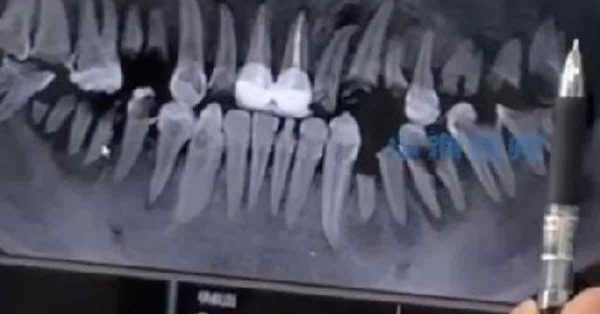

可乐当水饮 青年牙齿全部坏死

(武汉16日综合电)中国媒体周三报道,湖北省武汉市一名23岁男子因长期饮用大量可乐,导致牙齿龅坏及脱落,其中后牙几乎全部坏死,需进行手术拔出及种牙。医生建议民众喝无糖饮料,同时需控制摄取分量。

该名男子近日到武汉协和医院就诊,经检查发现,其后牙基本上已全被可乐腐蚀,并出现大面积的残根残冠。医生询问后获悉,男子平常有喝可乐及其他饮料的习惯,且每天喝2至3瓶可乐,几乎不喝水。医生只能保留男子目前仍能修复的牙齿,并拔除已溃烂至牙龈下方的牙。

口腔科医生孙明宇对此表示,可乐含有碳酸,会与牙齿中的钙质发生反应,继而腐蚀牙齿。他建议民众尽量不要喝含糖饮料,晚上睡觉前一定要刷牙。